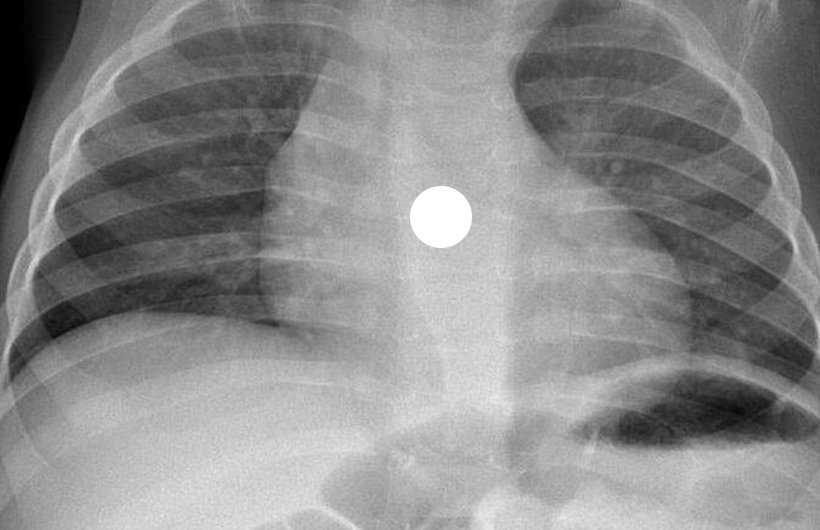

Foreign body removal is a bronchoscopic procedure to locate and extract any object accidentally inhaled (aspirated) into the airways. This may be food particles, small objects, medical devices, or teeth fragments after trauma/dental work. Aspiration can block airflow, cause infection, or even be life-threatening if not promptly treated.

• In children: peanuts, seeds, small toys, beads, coins.

• In adults: food particles, dentures, dental fragments, pins, medicinal tablets.